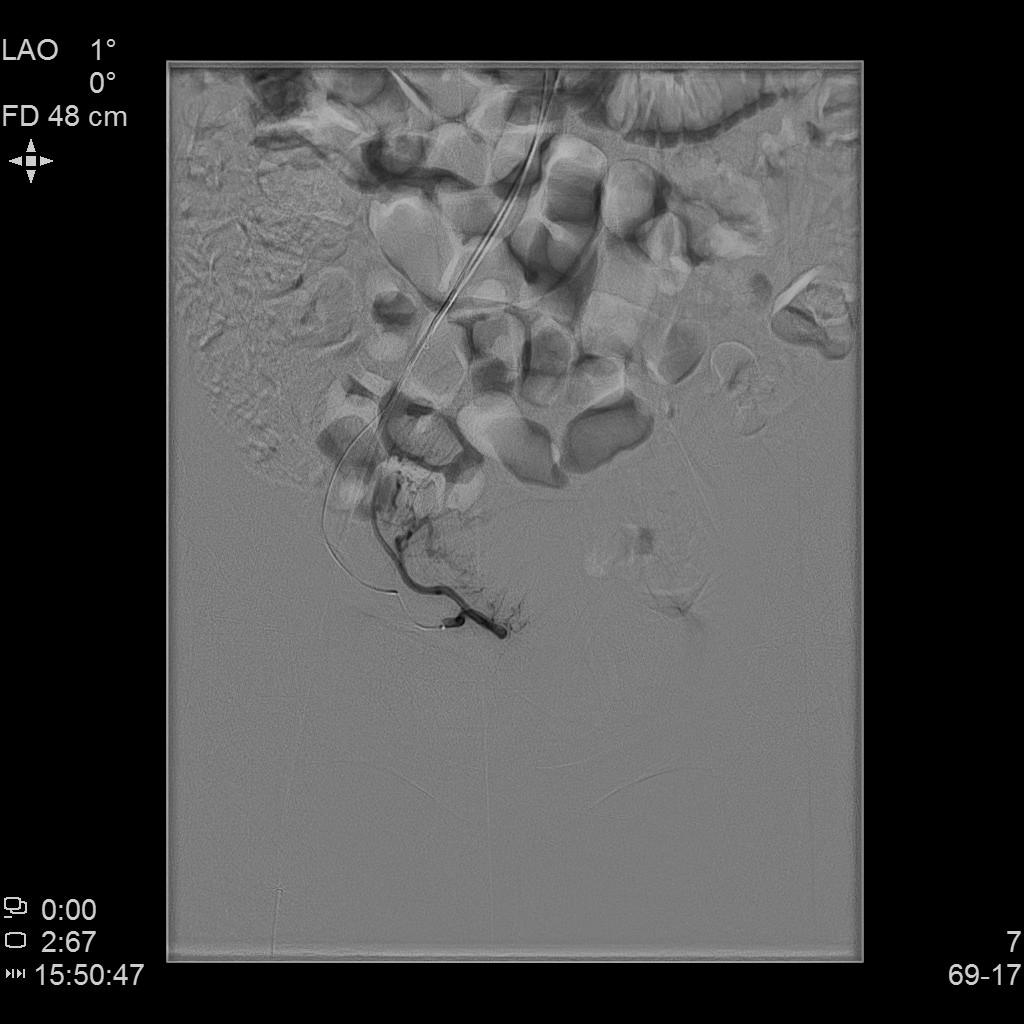

例4

中年女性,痛经10余年,近3个月明显加重。痛经达重度疼痛,严重影响生活质量。磁共振检查显示子宫前壁囊性病灶。临床诊断为囊性子宫腺肌症。

- 经左侧桡动脉穿刺置管,行腹主动脉造影显示双侧子宫动脉增粗、迂曲。

- 超选择插管右侧子宫动脉病灶供血动脉造影+栓塞治疗。

- 超选择插管左侧子宫动脉病灶供血动脉造影+栓塞治疗。

- 术后桡动脉压迫止血6小时,患者术后无需长时间卧床、下肢制动,舒适度明显提高,促进术后快速康复。